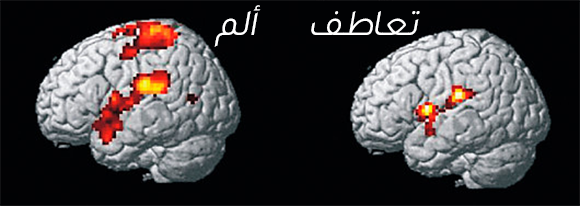

نشرت دراسة في مجلة "سانيس" Science أنّه تمّ العثور على دليل يشير إلى أنّ خلايا النيورونات المرآتيّة تشكّل أساس التّعاطف. وفقًا لدراسة، فإنّ مشاهدة شخص عزيز علينا يعاني من الألم الجسديّ، يؤدّي إلى تنشيط نفس المناطق في الدّماغ، الّتي تنشط عندما نعاني من الألم الجسديّ بأنفسنا. استخدم الباحثون في هذه الدّراسة التّصوير بالرّنين المغناطيسيّ الوظيفيّ (fMRI)، لقياس نشاط الدّماغ لدى النّساء وفيها تمّ تعريضهم لصدمة كهربائيّة مؤلمة في المعصم، وكذلك عندما شاهدن أزواجهنّ يمرّون بتجربة مماثلة. أظهرت النّتائج أنّ استجابة الدّماغ للألم كانت مماثلة في كلتا الحالتين.

يُعتبر الجزءان المسؤولان عن الألم في الدماغ هما القشرة الحزاميّة الأماميّة (Anterior Cingulate Cortex) والقشرة الجزيريّة (Anterior Insula)، وكلاهما يرتبط بالتّمثيلات العاطفيّة والوعي العاطفيّ. تقع القشرة الحزاميّة الأماميّة في الدّماغ بين القشرة الدّماغية والجهاز النّطاقيّ (Limbic System)، المسؤول عن العواطف والدّوافع. بينما تقع القشرة الجزيريّة عميقًا في الدماغ وتعالج الوعي للمشاعر الجسديّة، بما في ذلك الألم. تصل المعلومات الواردة من المناطق النّطاقيّة-العاطفيّة و القشرة الجزيريّة إلى القشرة الحزاميّة الأماميّة، وتساعد جميعها بالاشتراك مع قشرة الدّماغ في اتّخاذ القرارات.

تؤدّي مشاهدة أحد أفراد أسرتك وهو يعاني من الألم الجسديّ إلى تنشيط مناطق الدّماغ الّتي تنشّط أيضًا عندما نعاني من الألم الجسديّ ذاته بأنفسنا. صورة fMRI لدماغ شخص يشعر بالألم (يسار) أو رؤية شخص آخر يعاني من الألم (يمين)| Wellcome Centre Human Neuroimaging / Science Photo Library

إذا كان الأمر كذلك، فإنّ أحد أسباب صعوبة مشاهدة مقاطع الفيديو الّتي تحتوي مشاهد معاناة وألم الآخرين، قد ينتج عن تنشيط تجربة الألم في أذهاننا، حتّى لو لم نتعرّض للأذى بشكل مباشر. ينبع جزء من هذه الصّعوبة من العنصر العقليّ في فهمنا للعواقب المؤلمة للأحداث، وعدم اليقين بشأن المستقبل.

باختصار، عند مشاهدة مقابلة شخص ما، تنشط لدينا مناطق الدّماغ المسؤولة عن حركة عضلات الوجه وفقًا لتعابير وجهه، غالبًا بمساعدة الخلايا العصبيّة المرآتيّة، سواء كان حزينًا، متألمًا أو مصدومًا. بدورها، تنشّط تعابير الوجه الدّوائر الدماغيّة المرتبطة بالعاطفة الّتي تعكسها، وبالإضافة إلى معلومات من مناطق أخرى في الدّماغ، تنشأ لدينا مشاعر صعبة.